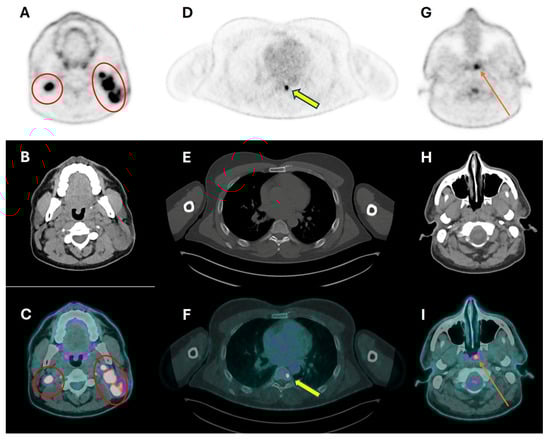

3.3. Distant Metastasis Assessment

- Barrett, T.F.; Gill, C.M.; Miles, B.A.; Iloreta, A.M.C.; Bakst, R.L.; Fowkes, M.; Brastianos, P.K.; Bederson, J.B.; Shrivastava, R.K. Brain metastasis from squamous cell carcinoma of the head and neck: A review of the literature in the genomic era. Neurosurg. Focus 2018, 44, E11. [Google Scholar] [CrossRef] [PubMed]

- Ishimori, T.; Patel, P.V.; Wahl, R.L. Detection of unexpected additional primary malignancies with PET/CT. J. Nucl. Med. 2005, 46, 752–757. [Google Scholar] [PubMed]

- Haerle, S.K.; Strobel, K.; Hany, T.F.; Sidler, D.; Stoeckli, S.J. 18F-FDG-PET/CT versus panendoscopy for the detection of synchronous second primary tumors in patients with head and neck squamous cell carcinoma. Head Neck 2010, 32, 319–325. [Google Scholar] [CrossRef]